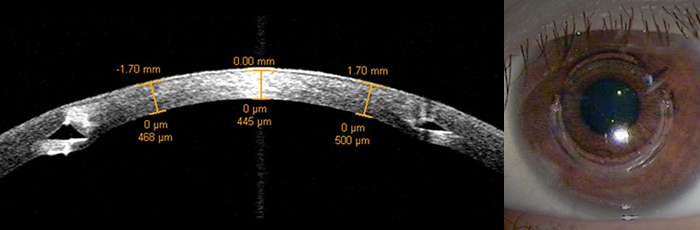

Advanced keratoconus patients may not be able to get adequate vision correction with contact lenses anymore and may need to find other treatment. One of those treatments, before considering corneal transplantation, is an intrastromal corneal ring (KeraRing) implant. This implanted ring flattens the cornea and reduces myopia as well as treats keratoconus. One or two rings are inserted into the cornea to reshape the front surface.

The KeraRing implants have the advantage of being removable and exchangeable. However implants are not recommended for those whose corneas are too thin. Although the implants can also correct astigmatism, as they are inserted much closer to the pupil, there is a possibility of blurred vision. This problem has been amended by designing the cross section to a prism shape. And for this technology, KeraRing has gained the European CE mark and has been KFDA approved.